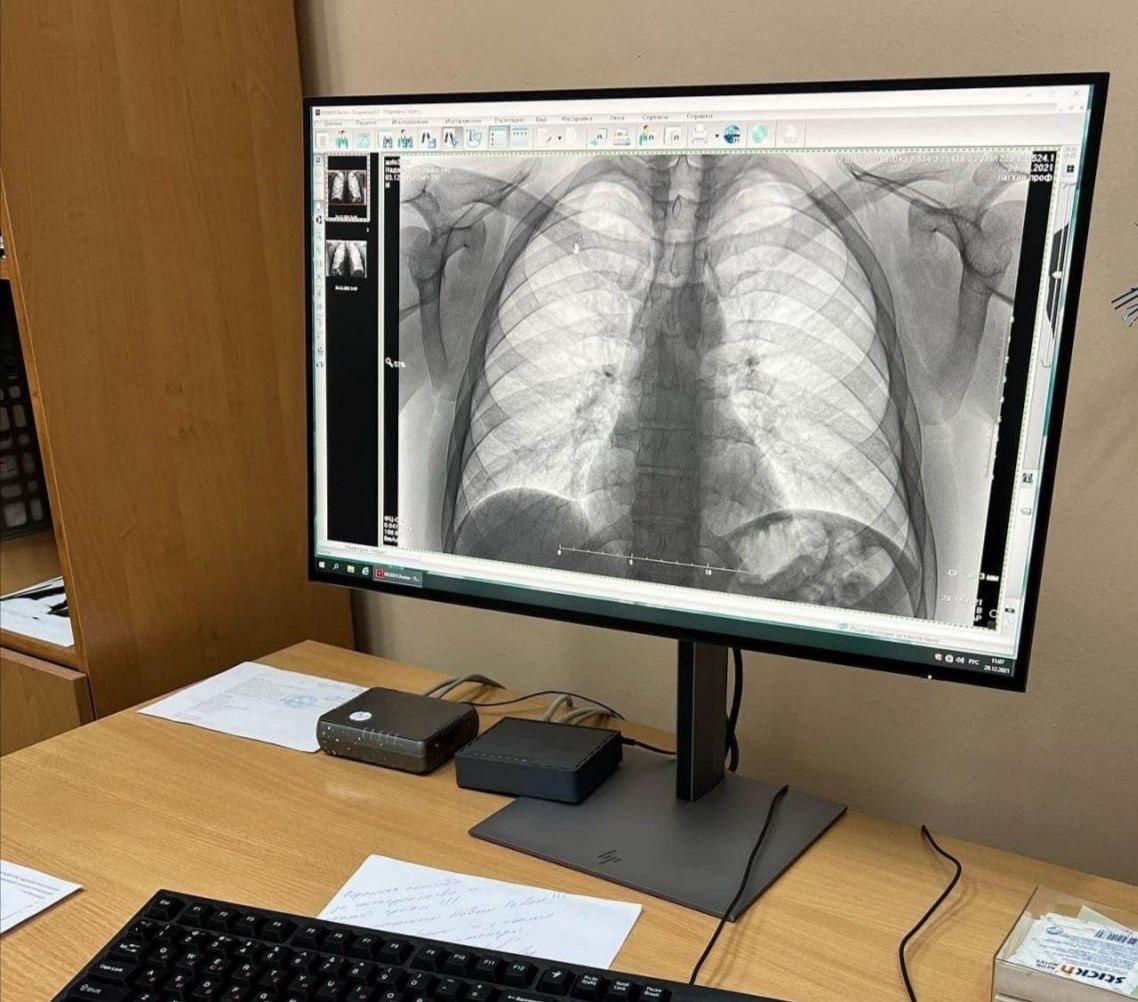

В Забайкальском краевом клиническом фтизиопульмонологическом центре 23 марта пройдет «День открытых дверей». С 10.00 до 15.00 забайкальцы смогут пройти флюорографическое исследование легких.